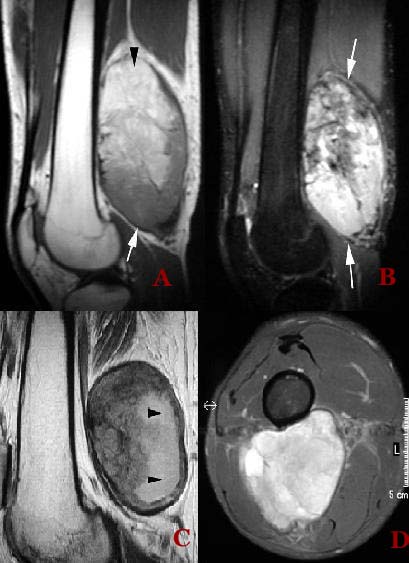

They are usually well seen on an MRI (go here ,here and here).

Patient with a large sarcoma in the right anterior thigh: CT here, MRI here and here, PET after neoadjuvant chemotherapy here and here

MRI Scan